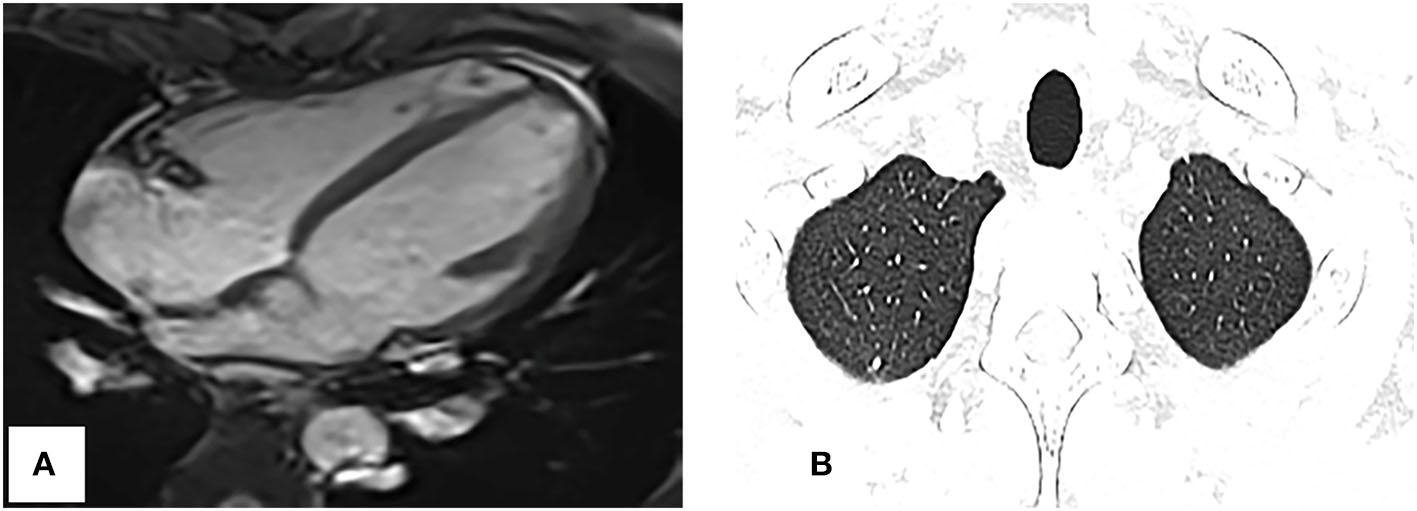

Follow-up period

Repeat CMRI and chest CT showed significant regression of the tumor and pulmonary metastases (Figures 5A,B). Now, the patient continues the chemotherapy and immunotherapy.

Figure 5

Repeat cardiac magnetic resonance imaging and thoracic CT. (A) SSFP cine imaging planned in the four chambers shows the tumor markedly reduced. (B) Thoracic CT shows the pulmonary nodules obviously decreased too, compared with Figure 1C.